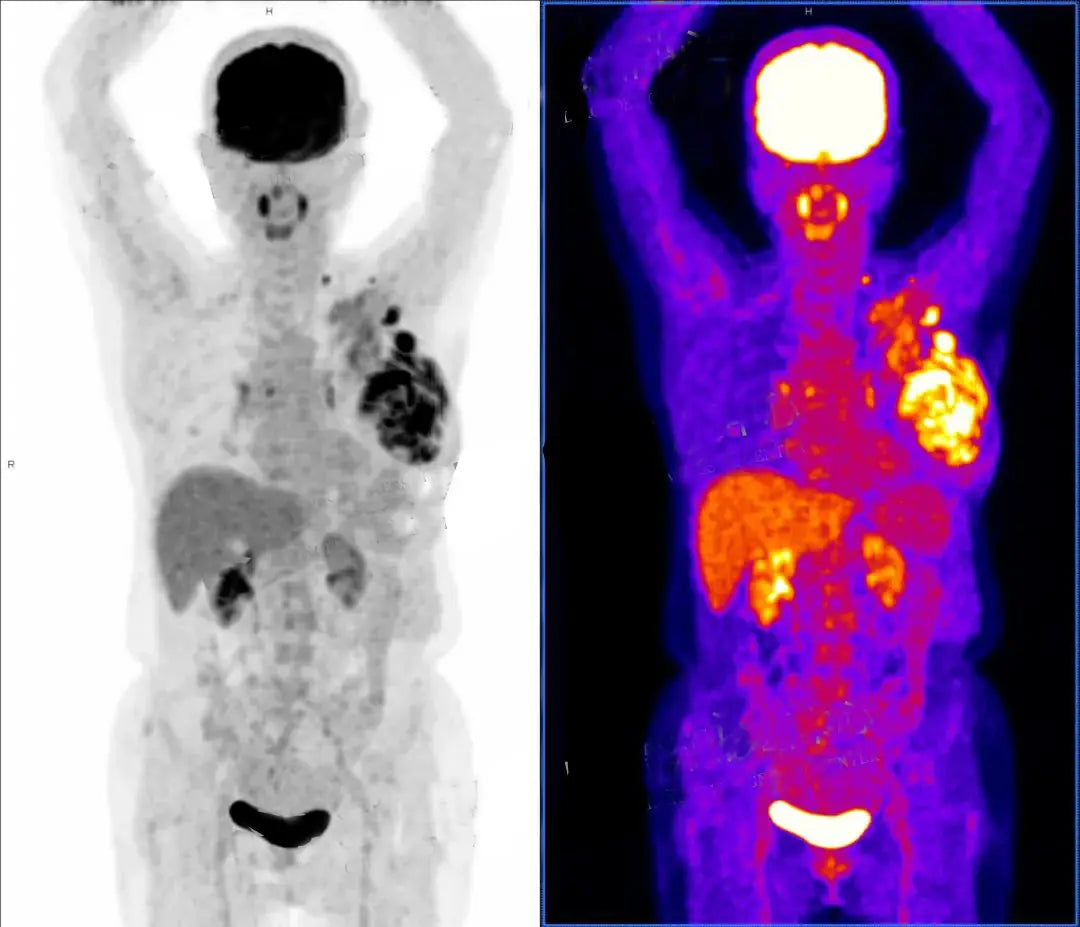

β—ˆ Primary Lesion Metabolism: Utilizing $^{18}\text{F-FDG}$ PET/CT to confirm irregular masses and evaluate metabolic activity to predict aggressiveness.

β—ˆ Local Anatomical Evaluation: Imaging confirms the mass has breached the deep fascia, invading the pectoralis major and localized skin.

β—ˆ Regional Lymphatic Mapping: Scanning the axillary, supraclavicular, and cervical Zone V regions to map metastatic lymph node distribution.